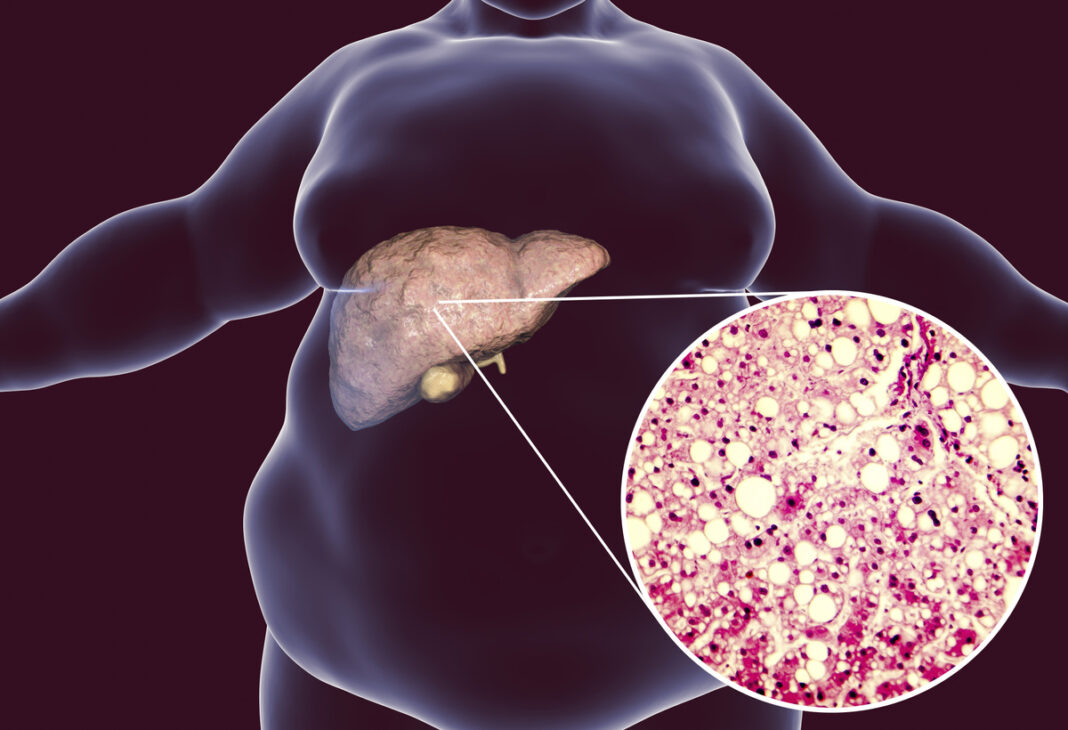

NASH constă într-o acumulare anormală de grăsime în ficat, declanșând o inflamație cronică a acestui organ. Celulele sale sunt înlocuite treptat de fibroză, un țesut cicatricial care poate la rândul său să degenereze în ciroză sau chiar în cancer.

Această boală este strâns legată de obezitate și reprezintă o piață uriașă pentru grupurile farmaceutice.